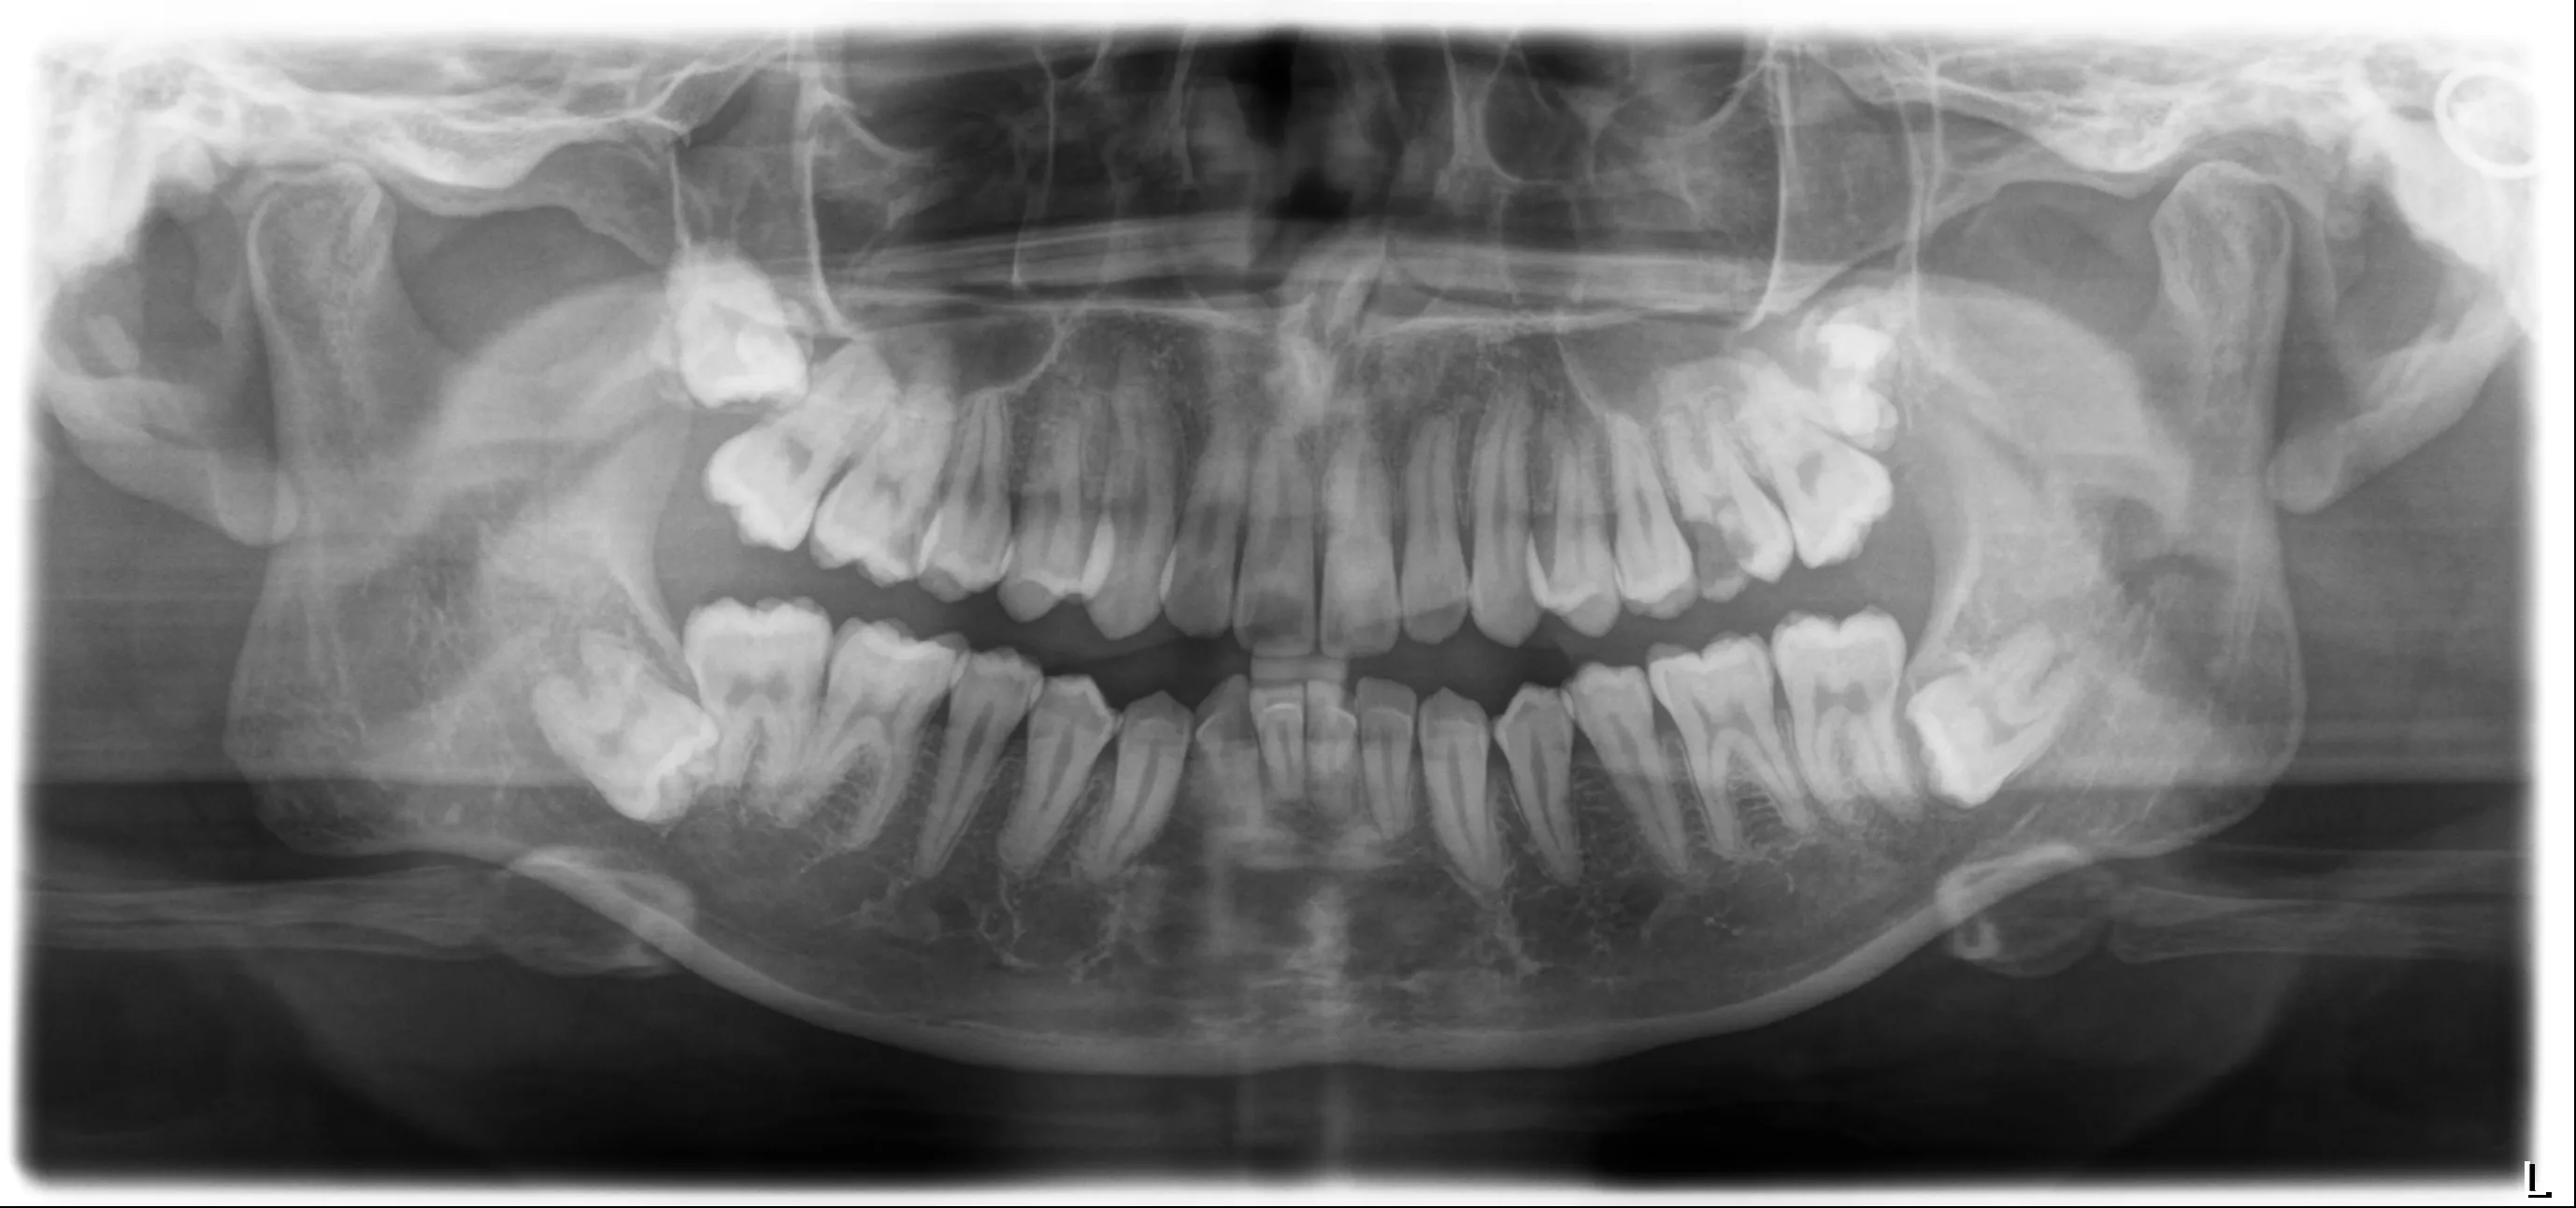

ココロデンタル恵比寿で実施した

インプラント症例

前歯欠損の症例

治療期間12ヶ月

Before

治療前の画像

After

治療後の画像

奥歯欠損の症例

治療期間8ヶ月

治療期間18ヶ月

被せ物が取れた症例

治療期間15ヶ月

ブリッジが外れた症例

治療期間10ヶ月